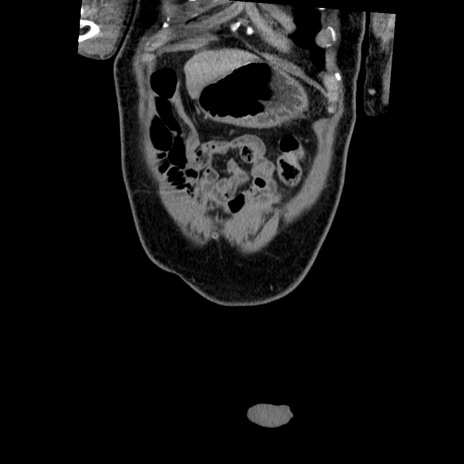

症例22(冠状断像)

【症例】50歳代男性

【主訴】腹痛

【現病歴】AVMからの被殻出血のため回復期リハ病棟入院中。 本日午後3時頃急に下腹部痛が出現した。

【既往歴】AVM、被殻出血、虫垂炎、高血圧

【身体所見】意識晴明、左半身不全麻痺、会話の理解は良好、36.5°C、腹部:膨隆、全体に板状硬、下腹部正中に圧痛点あり、反跳痛-、筋性防御不明、右下腹部にope scar

【データ】WBC 9400、CRP 0.06